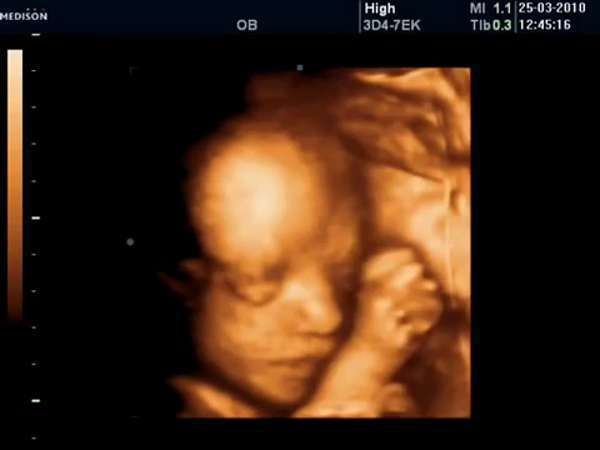

26 Haftalık Bebek

26 haftalık hamilelikte 3d , 4d boyutlu ultrason görüntüsü. 26 hafta gebelik ultrason görüntüleri 26 haftalık gebelikte anne karnında bebeğin görüntüsü, 26 haftalık ayrıntılı ultrason görüntüsü.